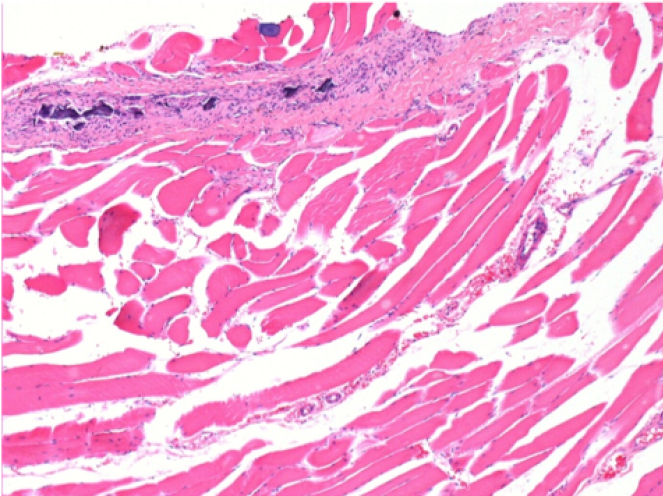

Л: Претибіальний м'яз - без лікування

Через 10 днів після ін'єкції Ендопіл 0,1 мл в правий претибіальний м'яз.

Тут можна побачити утворення вакуолей, які оточені лімфоцитами. Вакуолі відрізняються від некрозу тканини. Присутність лімфоцитів пов'язана з проникністю клітинних мембран.